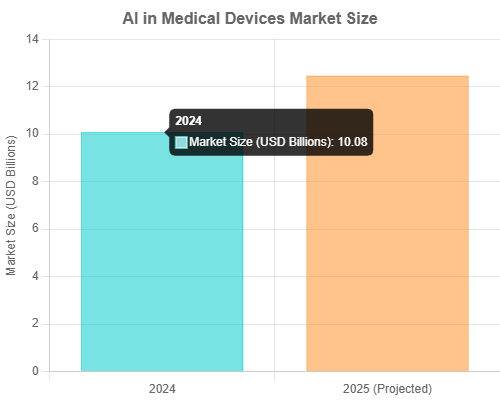

The market for AI in medical devices reflects this rapid adoption. According to The Business Research Company, the market size is projected to grow from $10.08 billion in 2024 to $12.46 billion in 2025, demonstrating significant year-over-year growth (The Business Research Company, 2025 Report). This financial momentum is fueled by AI’s ability to improve image quality, reduce scan times, assist in diagnoses, and even guide surgical procedures (MedTech Dive, Oct 9, 2024).